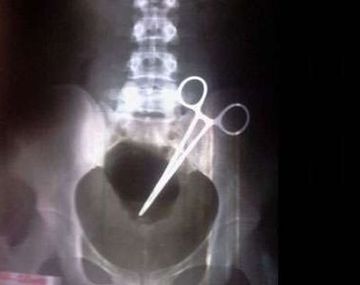

Una mujer vive con una tijera en el abdomen hace 9 meses Le practicaron una cesárea en un sanatorio de La Rioja. Comenzó a sentir molestias y una radiografía descubrió que tenía en el cuerpo un elemento de 15 centímetros. La Rioja